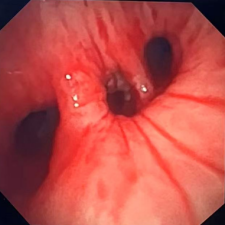

在患者入院后,呼吸与危重症医学科对患者进行了进一步检查。在高流量吸氧80%条件下,患者静息氧饱和度仅能维持在80-85%左右,床旁胸片显示右肺完全不张可能,呼吸与危重症医学科介入团队评估后,决定立即进行急诊手术准备。一方面与家属积极沟通,交代病情和风险,另一方面与麻醉科、微创手术平台联系,做好各环节衔接准备,并沟通抢救预案。2025年5月23日上午,手术在微创中心(第二手术区)正式开始。入室时,患者血氧饱和度仅有68%,伴有神志淡漠,意识恍惚。麻醉师迅速给予全麻,呼吸介入团队马上进行进镜探查。镜下发现患者右主支气管被肿物完全阻塞,伴有血性分泌物。在微创手术室护士的配合下,呼吸介入团队用电圈套器、电刀、冷冻冻切等多种方法,迅速打通了气道。经过45分钟的手术,患者氧饱和度已恢复至97%。手术成功。

治疗后右中下叶复通